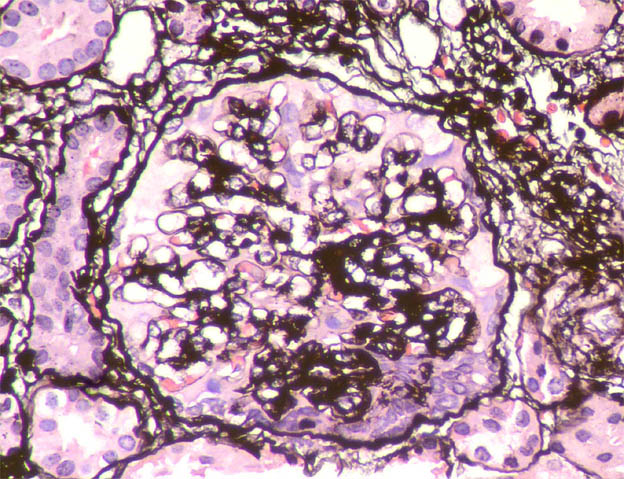

The patient is a 11-year-old boy with a history of steroid-resistant nephrotic syndrome since he was 7 years old. Renal biopsy at 8 years was diagnosed as focal segmental glomerulosclerosis (in another center, we do not have histological images). He continues with nephrotic syndrome since and now the serum creatinine has increased: 1.4 mg/dL. A new renal biopsy is undertaken to see the severity of the histological changes and decide whether to try another immunosuppressant treatment.

See the images of the second renal biopsy.

Figure 6. Methenamine-silver, X400.